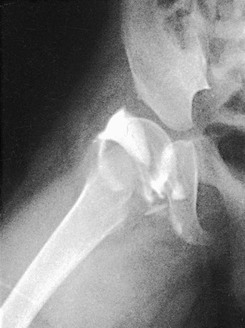

Hip arthrography is most often performed on children in a surgery suite by an orthopedic surgeon. Arthrography is used to evaluate lateral femoral head displacement and after closed reduction to ensure that there is no folding or impingement of soft tissues (see Fig. 12-2, pretreatment) (Figs. 12-14 and 12-15, post-treatment). In adults, the primary use of hip arthrography is to detect a loose hip prosthesis or to confirm the presence of infection. The cement used to fasten hip prosthesis components has barium sulfate added to make the cement and the cement-bone interface radiographically visible (Fig. 12-16). Although the addition of barium sulfate to cement is helpful in confirming proper seating of the prosthesis, it makes evaluation of the same joint by arthrography difficult.